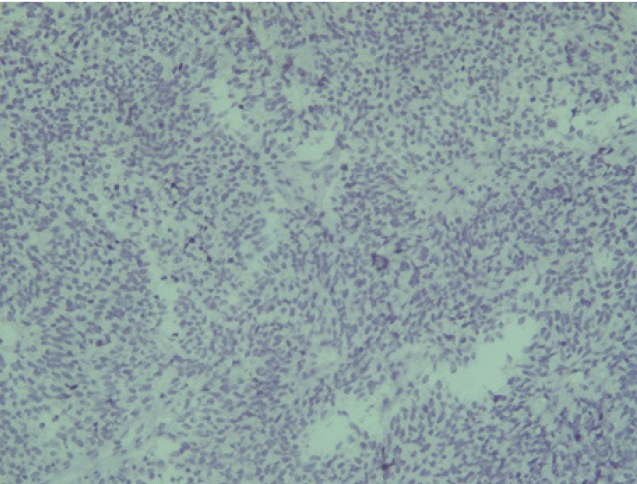

Поэтому при первичном гистологическом исследовании диагноз эстезионейробластомы был установлен только у 6 пациентов (66,6 %), у троих больных (33,4 %) были диагностированы другие формы злокачественного процесса, что не соответствовало клиническим проявлениям. Во всех случаях проводили иммуногистохимическое (ИГХ) исследование. ИГХ-исследование проводили на срезах с парафиновых блоков с использованием антител к Keratin.Pan (AE/AE3), CD45 (Cocktail), Synaptophysin (SP11), ChromograninA (SP12), CD56 (56C04), Ki-67 (30-9), p63 (7JUL)RTU, S100, INI1, CD99 (HO36-1.1). Также выполняли доставку с антителами к EMA (E29), TTF1 (8G7G3/1). В диагностических материалах была отмечена положительная экспрессия Synaptophysin, ChromograninA, CD56, Ki-67 (до 90% ядер), INI1 (рис. 2–6).

Отрицательная экспрессия была отмечена в диагностических образцах с использованием антител к Keratin.Pan, CD45, p63, S100, EMA (E29), TTF1(рис. 7–12).

Рис. 2. Synaptophysin [SP 11] ×200

Рис. 3. Chromagranin A [SP 12] ×200

Рис. 4. CD 56 [56C04] ×200

Рис. 5. Ki-67 [30-9] (90%) ×200

Рис. 6. INI 1 ×200

Рис. 7. Keratin.Pan [AE/AE3] ×200

Рис. 8. CD 45 [Cocktail] ×200

Рис. 9. p63 [7JUL] RTU ×200

Рис. 10. S100 ×200

Рис. 11. EMA [E29] ×200

Рис. 12. TTF1 [8G7G3/1] ×200

Эти результаты иммуногистохимического исследования подтверждают наибольшее соответствие иммунофенотипа опухоли – ольфакторной нейробластоме (G3 по Hyams) М9522/33.